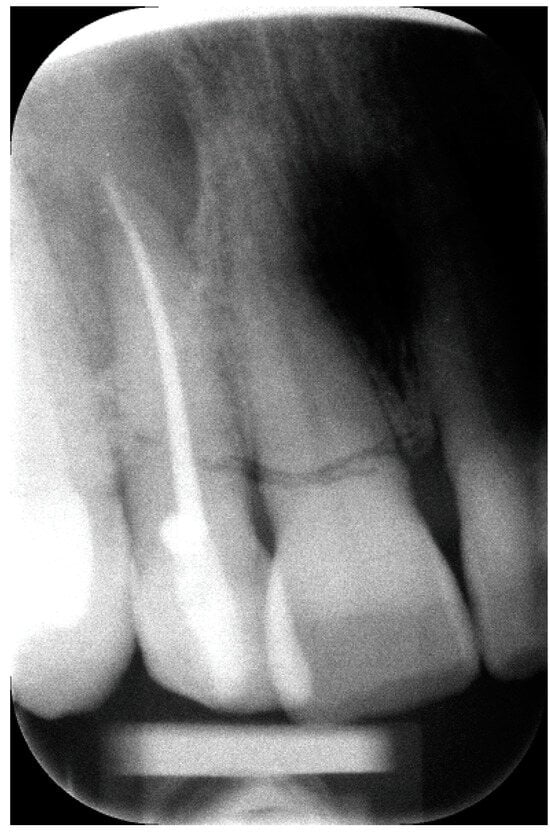

2. The Case